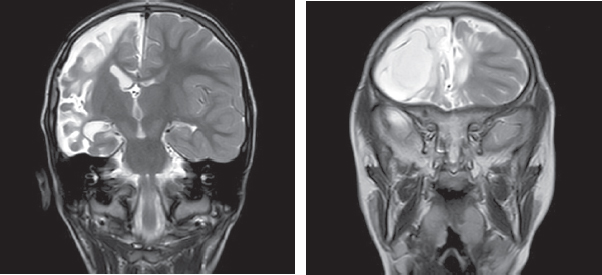

Актуальность изучения последствий геморрагических инсультов у детей раннего возраста обусловлена частотой цереброваскулярной патологии, формированием стойкого неврологического дефицита, в том числе постинсультной эпилепсии, высокой летальностью. Известно, что геморрагии диагностируют в первые 28 дней жизни у 6,7 из 100 000 младенцев, у детей с 28-го дня жизни до 18 лет — от 0,7 до 5,1 случая на 100 тыс. детского населения. Летальность при геморрагических и ишемических инсультах у детей составляет от 7 до 28 %. Эпилептические приступы острейшего и острого периода инсульта — прогностически неблагоприятные факторы течения заболевания. В статье приведены краткие литературные данные об этиологии и локализации геморрагических инсультов, их роли в формировании фармакорезистентной эпилепсии. Особое внимание уделено роли поздней геморрагической болезни новорожденных, сопровождающейся внутричерепными кровоизлияниями, в формировании структурной эпилепсии в последующем. В работе представлены также собственные клинические наблюдения 25 пациентов, страдающих эпилепсией, после перенесенного геморрагического инсульта с описанием клинической картины, особенностей пароксизмальных состояний и их терапии, данных нейровизуализации, электроэнцефалографических феноменов. Представлен клинический пример, в котором рассмотрены клинико-анамнестические, электрофизиологические данные пациента с фармакорезистентной эпилепсией, развившейся вследствие перенесенного геморрагического инсульта на фоне поздней геморрагической болезни новорожденных.

Структурная эпилепсия у детей, формирующаяся после перенесенного геморрагического инсульта, сопровождается значимыми мультирегиональными повреждениями, выраженным неврологическим дефицитом и характеризуется фармакорезистентным течением.